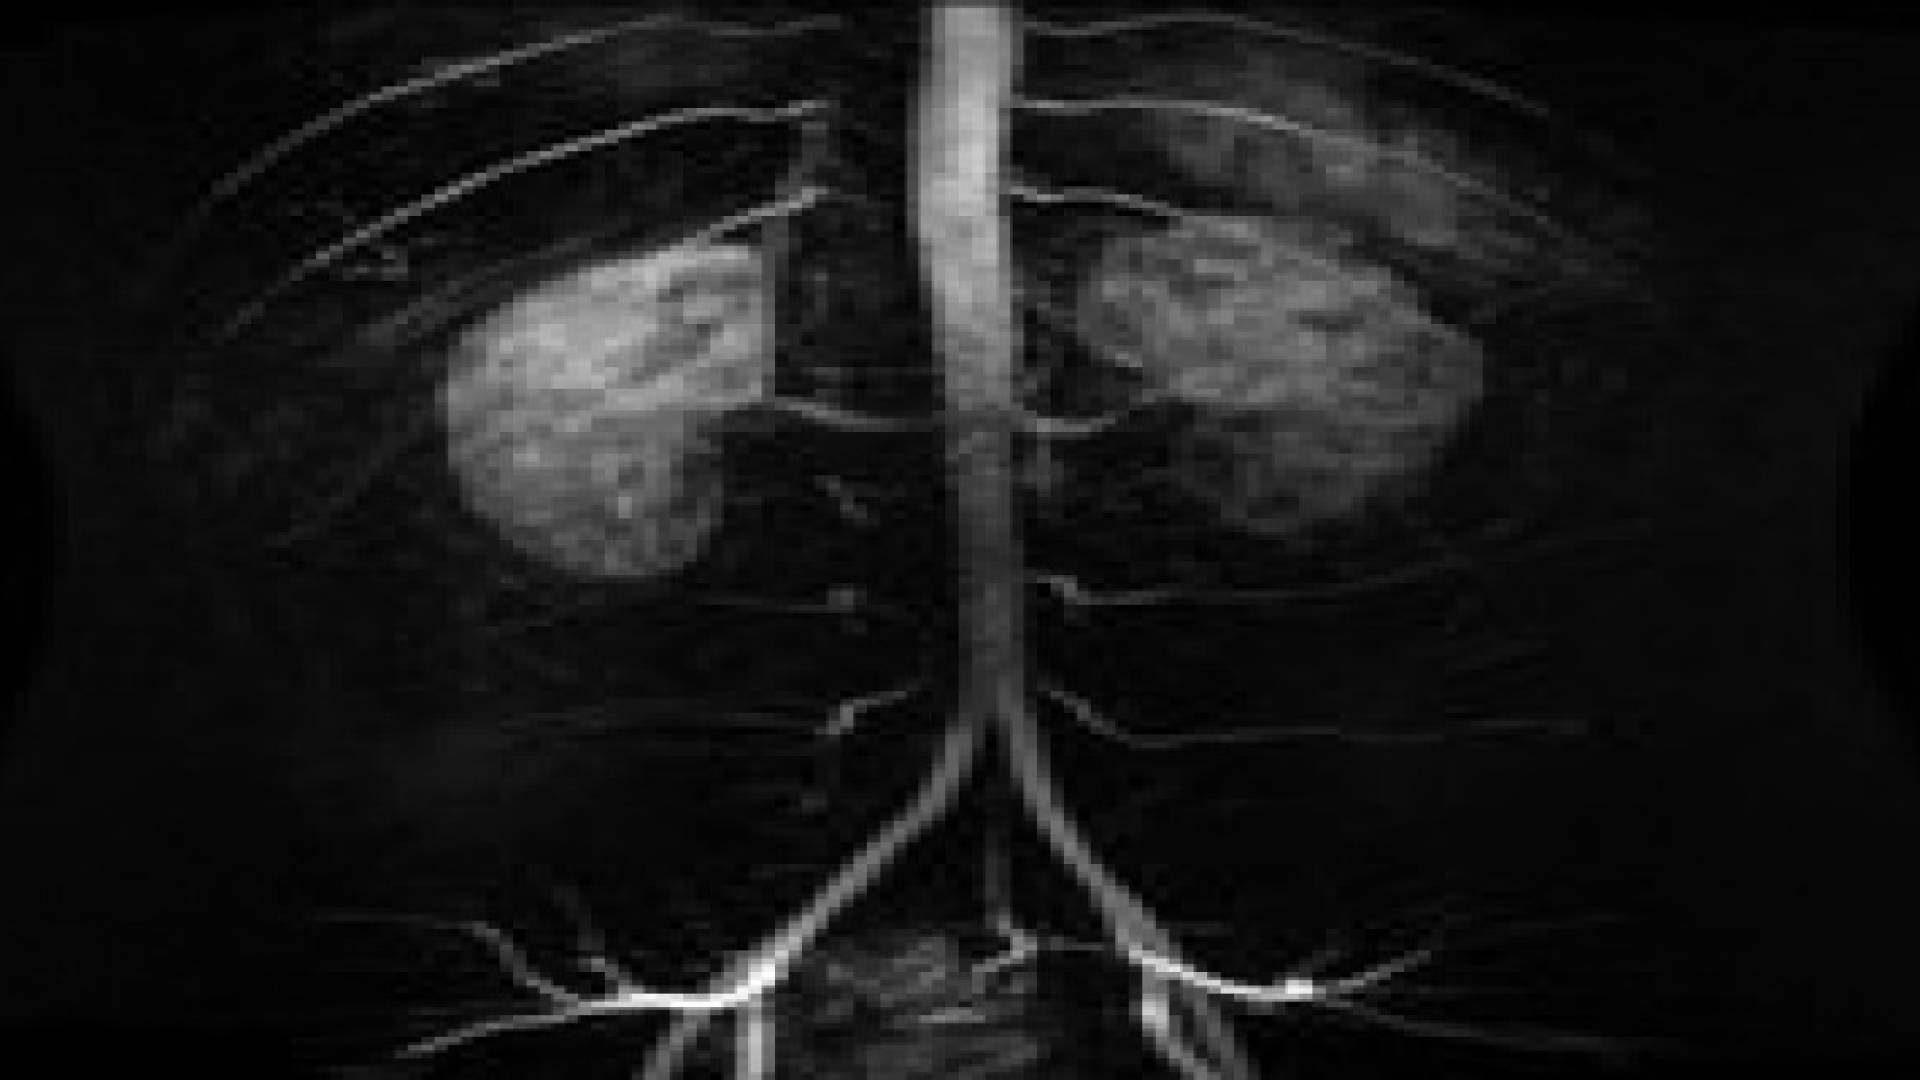

ويعد الشريان الأبهر (الأورطي) أكبر شريان في الجسم، وتعود أهمية هذا الشريان لكونه ينقل الدم الغني بالأكسجين من القلب إلى كافة أعضاء الجسم. ولكن أحيانا يتمدد جدران الشريان في مناطق معينة وتتشكل أكياس تنفجر وتؤدي إلى تمزق المنطقة الضعيفة من الشريان، مما يشكل خطرا كبيرا على الحياة، وهو ما يعرف بمرض تمدد الشريان الأورطي أو "أم الدم".

ولتجنب هذه المخاطر يسعى الأطباء في ألمانيا إلى استخدام دعامة خاصة للشريان الأبهر، وهي أحدث تقنية علاجية يمكن أن تنقذ المريض من الخطر حسبما يؤكد إنغو فليسنكريكمبر، مضيفا أن الدعامة ليست موحدة ويتم تصنيعها بدقة وفقا لحالة كل مريض. ومن خلال شق صغير في منطقة تشابك الأوعية الدموية يدفع الأطباء الدعامة الصناعية في المنطقة المصابة، وبذلك يكون التدخل الجراحي بسيطا ومخاطره أقل.